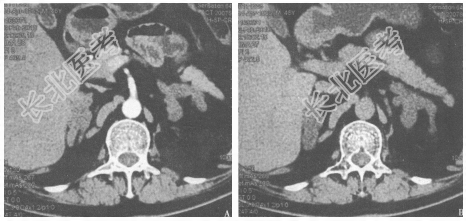

- 简答题2、患者完善了腹部+盆腔CT检查(图7)。下一步还需做哪些检查以进一步明确诊断

- 简答题3、内分泌检查结果如下:血浆ACTH<1.1pmol/L。皮质醇节律消失(0点皮质醇2.86pmol/L),24小时尿游离皮质醇868.76nmol/24h(正常值33.95~285.66nmol/24h),小剂量地塞米松抑制试验不被抑制。24小时尿儿茶酚胺正常。硫酸脱氢表雄酮2.6μmol/L(正常值0.60~6.92μmol/L)。目前该患者最可能的诊断是